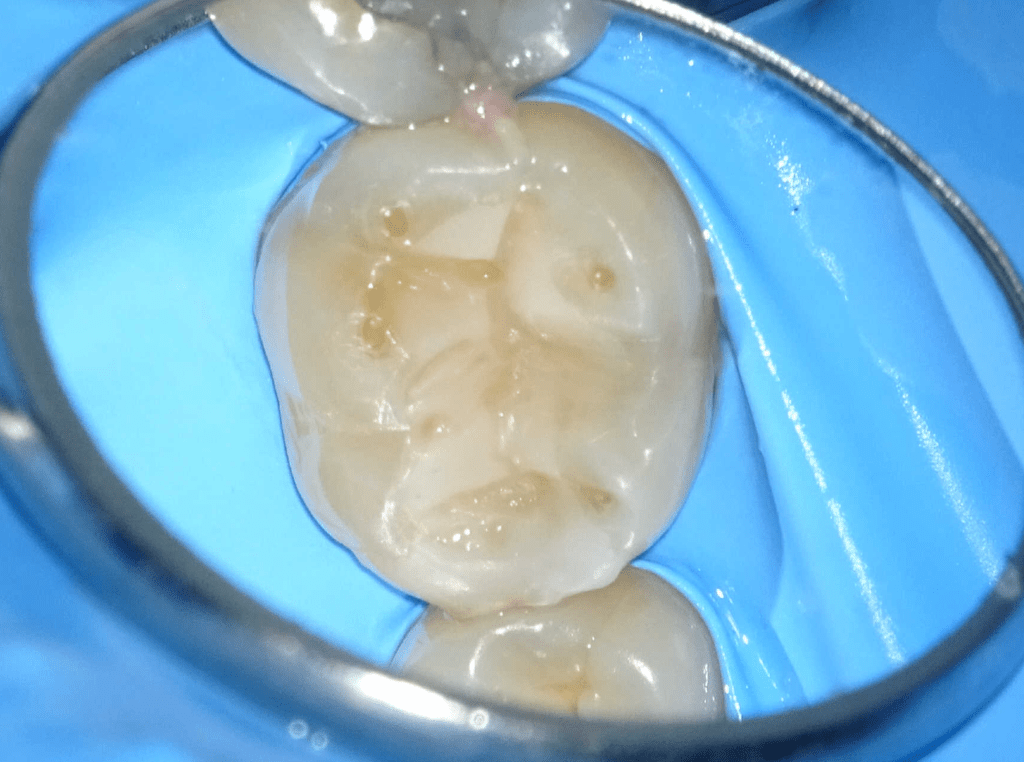

Fisura, remoción amalgama para explorar